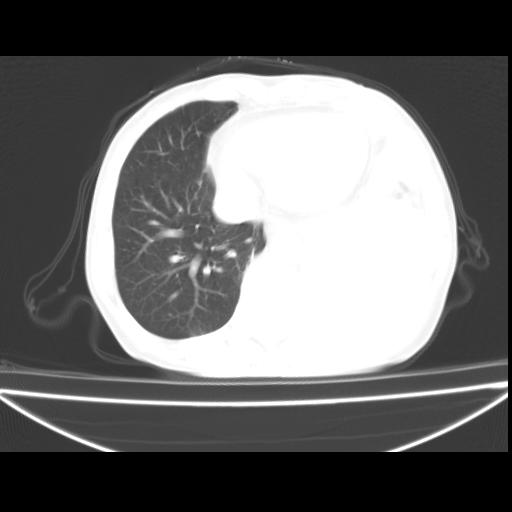

以下是引用随光逐影在2010-3-24 19:15:00的发言:[br]结合病史,考虑双肺及纵隔淋巴结多发转移、左侧胸膜转移并左侧大量胸水,左下肺膨胀不全。

以下是引用zxl51642在2010-3-24 18:49:00的发言:[br]结合乳腺癌术后病史,考虑双肺及纵隔淋巴结多发转移、左侧胸膜转移并左侧大量胸水、左下肺膨胀不全。